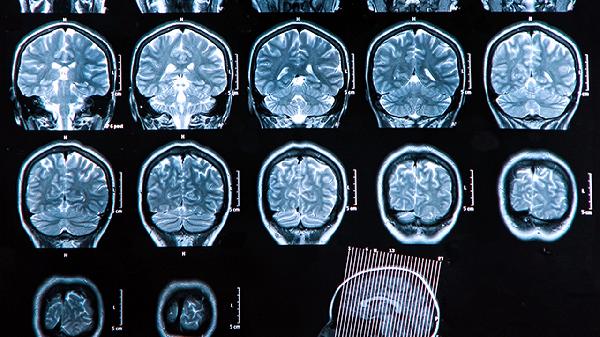

换二尖瓣手术的风险包括麻醉风险、感染、出血、血栓形成、心律失常及心脏功能不全等。高龄患者、合并糖尿病、高血压、肺病或其他心脏疾病的人群风险相对较高。术前医生会进行全面评估,包括心电图、心脏超声、血液检查等,以确定手术可行性。